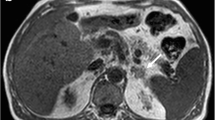

The most appropriate first-line test is the measurement of plasma free or and urinary fractionated metanephrines. As >95% of pheochromocytomas originate in the adrenal glands, CT is the main modality that has been recommended. MRI examination can be performed when radiation dose is a consideration or if metastatic disease is suspected [11,12,13,14, 38, 40]. Most pheochromocytomas are moderate-sized tumors and have imaging appearances that overlap with that of other solid tumors such as ACC and metastases as shown in Fig. 10.4a [15, 38]. In patients with MEN and vHL, the tumors are small and multicentric [38].